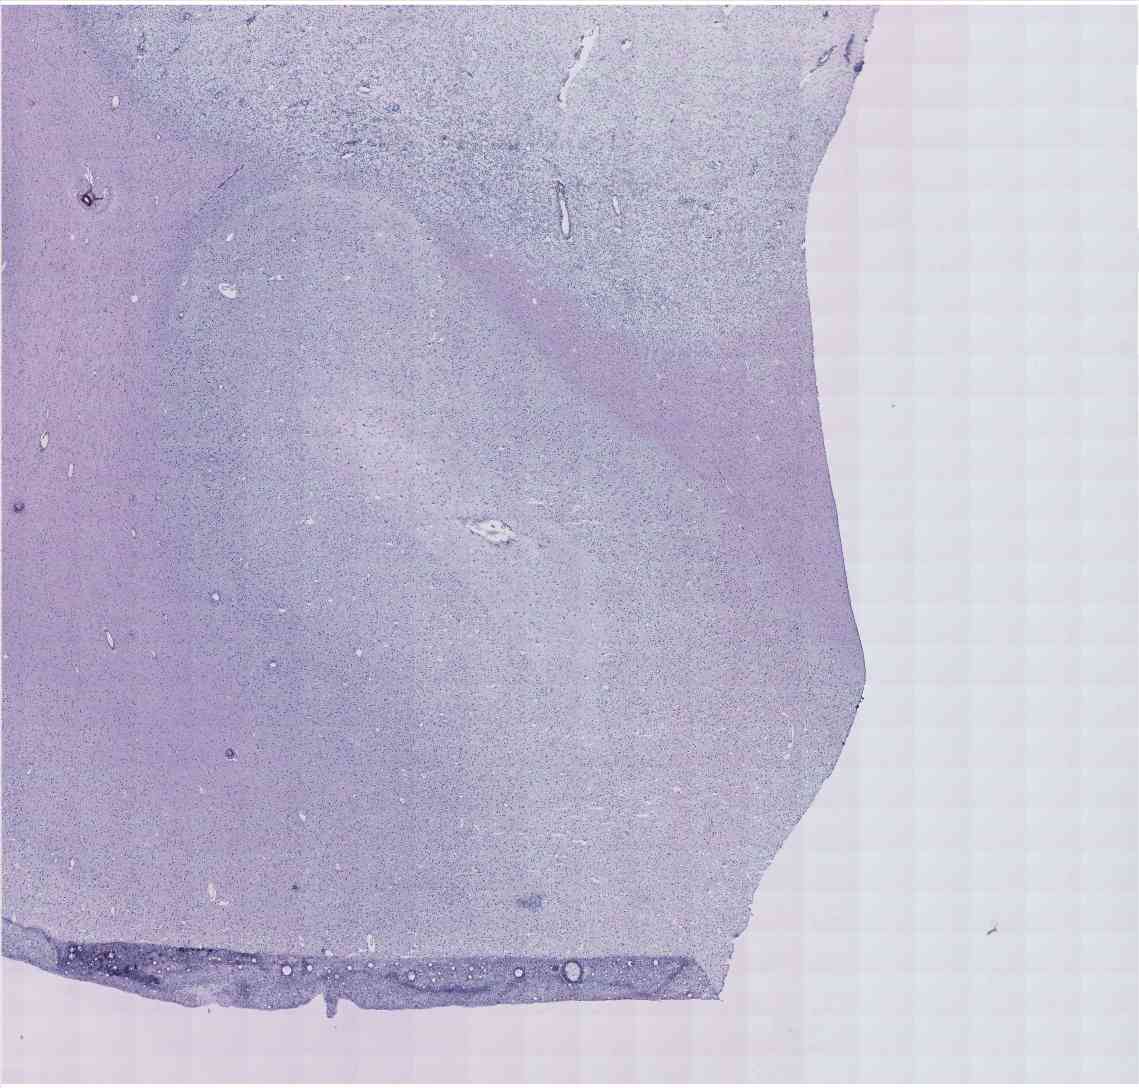

Chip 026 Well E2